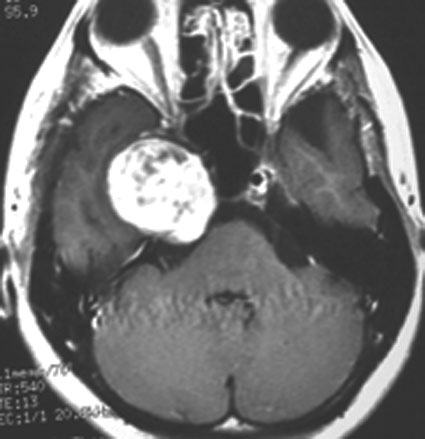

上顎洞癌と間違えるようなもの

三叉神経鞘腫は,頭蓋底の孔(上眼窩裂,正円孔,卵円孔)から眼窩内や頭蓋底,鼻咽腔に伸びることがあります。CTで頭蓋底骨の孔の拡大があることで診断がつきます。bone erosionといって徐々に大きくなる腫瘍の特徴的な所見です。

左上顎癌と間違えそうなMRI画像です。CTでは左の正円孔(黄色の矢印)が辺縁が滑らかに拡大 erosion しているので三叉神経第2枝(上顎神経)の神経鞘腫の診断がつきます。